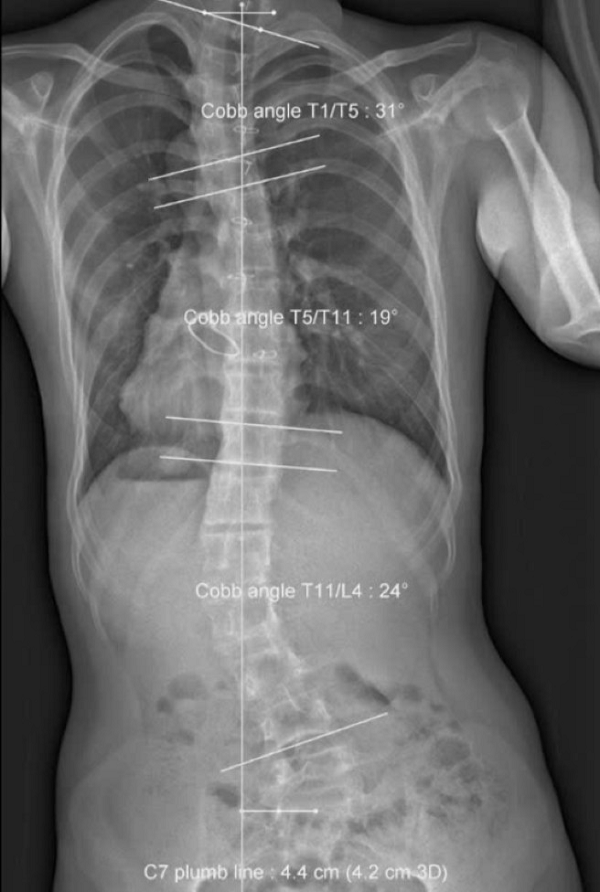

| Ảnh chụp cột sống cho thấy bệnh nhân bị vẹo hình chữ S. Ảnh: BSCC. |

Tại trung tâm, kết quả chụp X-quang cho kết quả trẻ bị lệch vẹo nghiêm trọng tất cả khớp cổ chân, khớp gối; khung chậu nghiêng xoay; cột sống cong vẹo chữ S trên 40 độ.

Sau 20 buổi tập, bệnh nhân đã có cải thiện rõ rệt, khung chậu bớt nghiêng trái. Sau 40 buổi tập, khung chậu đã cân bằng, cột sống đã cải thiện, giảm vẹo hẳn gần 20 độ, thân đã thẳng trục trở lại.